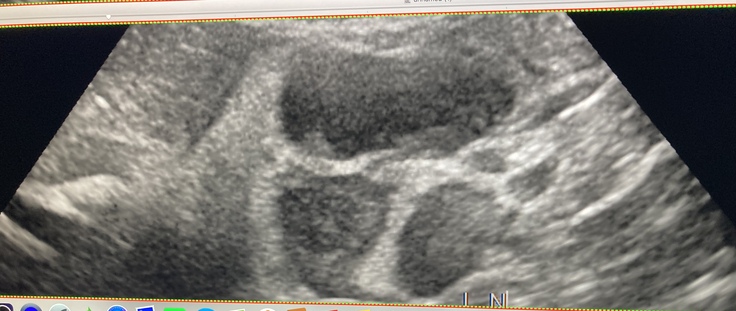

11月18日 動物病院受診 検査

11月19日 1回目抗癌剤治療

11月21日 高グレードリンパ腫(悪性リンパ腫)診断

11月18日前 病院受診時の異変

嘔吐

病院診断書

11月20日 検査 1回目 抗癌剤治療